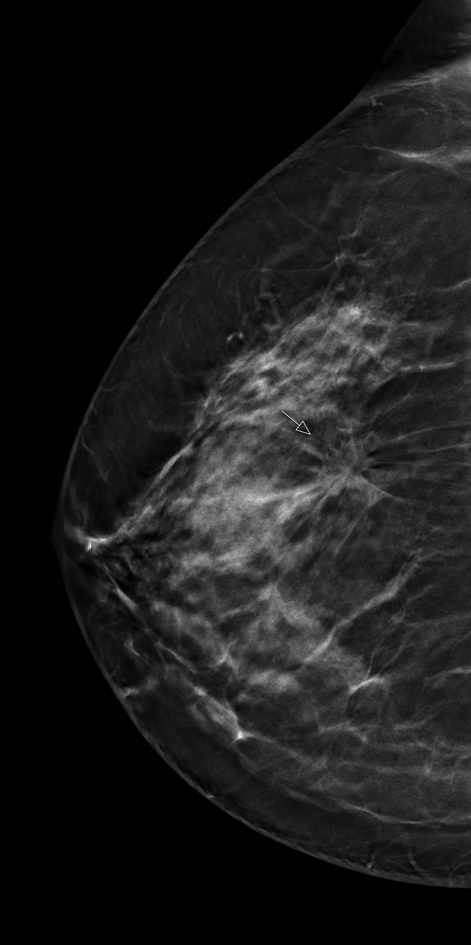

Führt die Verbesserung digitaler Techniken zur Früherkennung von Brustkrebs auch zu Effizienzsteigerungen im Mammographie-Screening? Diese Frage steht im Fokus eines groß angelegten Forschungsprojektes der Radiologie am Universitätsklinikum Münster (UKM): In der sogenannten ToSyMa-Studie wird geprüft, ob die technische Weiterentwicklung der digitalen Mammographie zum Schichtbildverfahren (digitale Brust-Tomosynthese) den derzeitigen Standard der zweidimensionalen mammographischen Brustuntersuchung im Screening voranbringt. Geplant ist, 80.000 anspruchsberechtigte Frauen zwischen 50 und 69 Jahren, die sich für eine Teilnahme am Screening entschieden haben, für die Datenerhebung zu gewinnen. Die von einem interdisziplinären Team der Universität Münster entwickelte diagnostische Studie wird von der Deutschen Forschungsgemeinschaft (DFG) gefördert.

„Mit der Weiterentwicklung der digitalen Mammographie zur Brust-Tomosynthese steht eine Technologie zur Verfügung, die durch die Berechnung dreidimensionaler Datensätze potenzielle Gewebeüberlagerungen in der Brust reduziert und daher diagnostische Vorteile bieten kann. Erste Ergebnisse aus ToSyMa werden Ende 2020 erwartet, abschließende im Jahr 2023“, sagt Prof. Walter Heindel, Direktor des Instituts für Klinische Radiologie (IKR) der Uniklinik Münster. Der Projektname ist eine Abkürzung und leitet sich ab aus dem englischen Titel der Studie („Digital breast tomosynthesis plus synthesised images versus standard full-field digital mammography in population-based screening“).